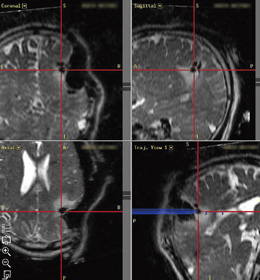

図3 術中撮像

麻酔器と生体モニタを除く電子機器の電源をすべて落とし,MRIを撮像する(a,b)。

T2強調像は約4分,3Dの造影T1強調像は約9分で撮像し,DICOM形式で保存して,ニューロナビゲーションシステムに転送する。